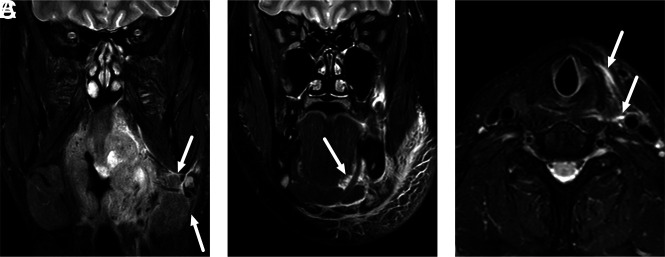

FIG 2.

Examples of uncomplicated PTA (A) and abscesses with deep extension (B–D) in different patients. In uncomplicated PTA, the abscess is retained within the pharyngeal constrictor muscle (A). In axial images, a deeply extending PTA is often lobulated and reaches laterally toward the parapharyngeal space, beyond the pharyngeal constrictor muscle (B). In sagittal images, a deeply extending PTA can reach far inferiorly (C) or superiorly (D) from the palatine tonsil (asterisk). The arrows denote abscesses.